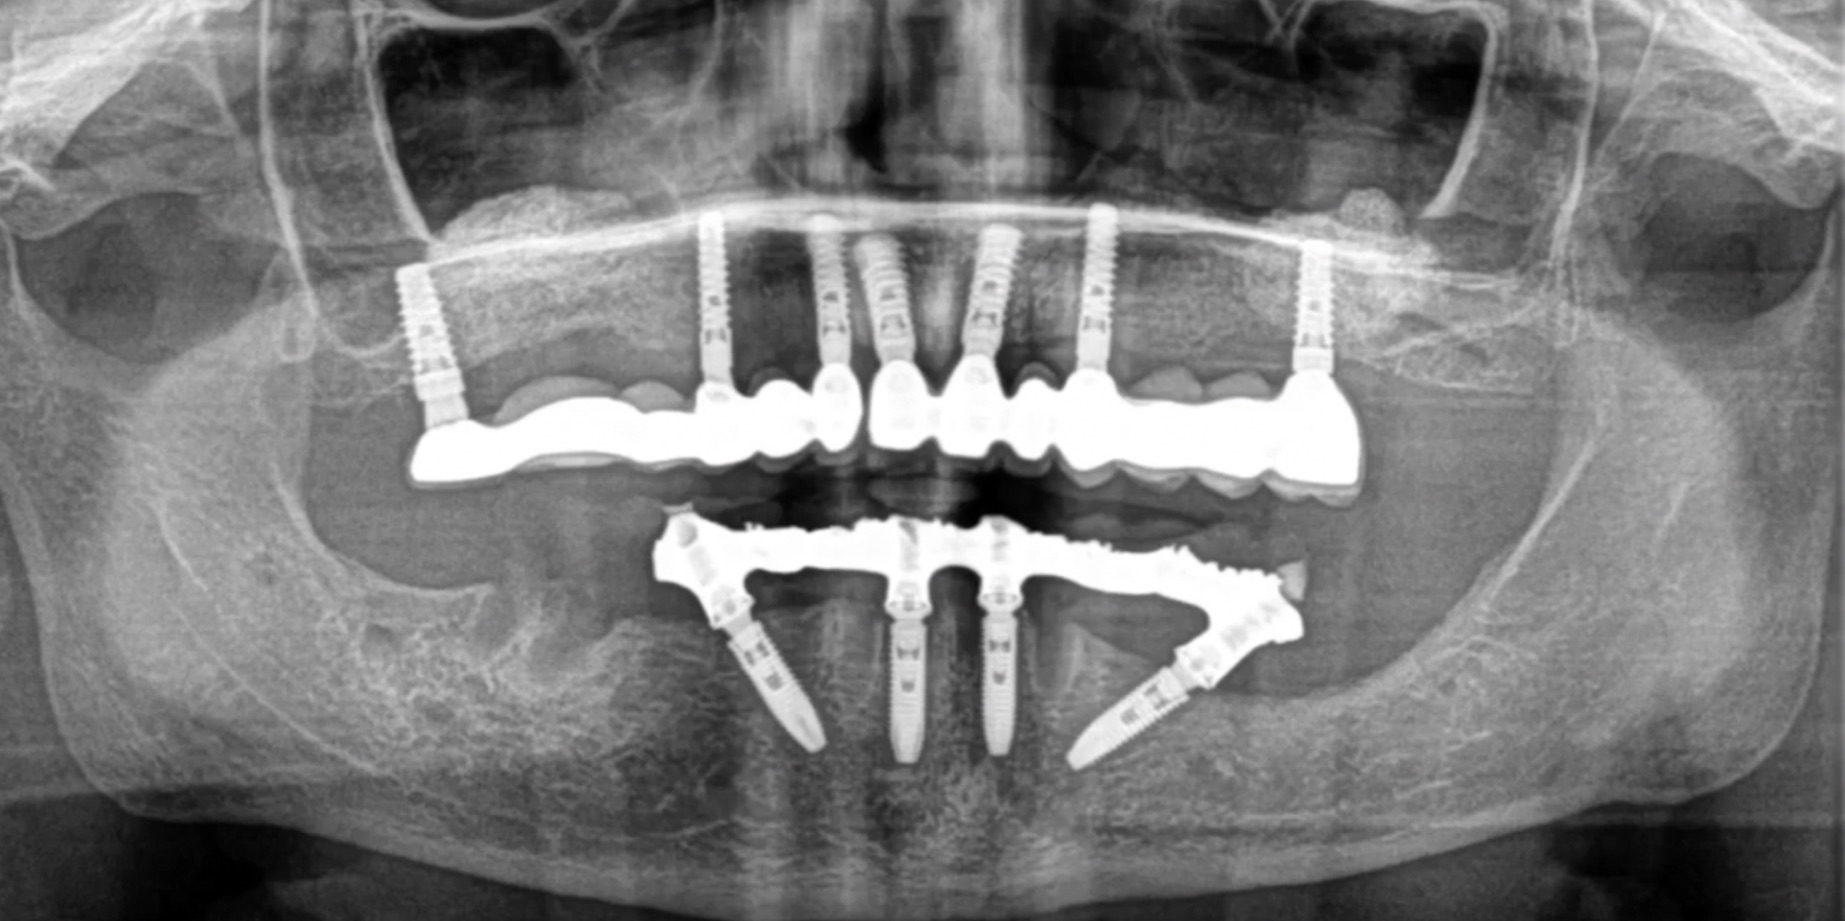

In this case presentation, the patient

suffered from a failed dentition in the maxilla and is planned to be restored with an

implant retained fixed hybrid denture. This video demonstrates the step-by-step

approach of the implant placement in the maxilla, including a titled implant

to avoid the sinus. Plaster impression was taken immediately after surgery and

an immediate temporary metal-acrylic denture was fixed to the implants.